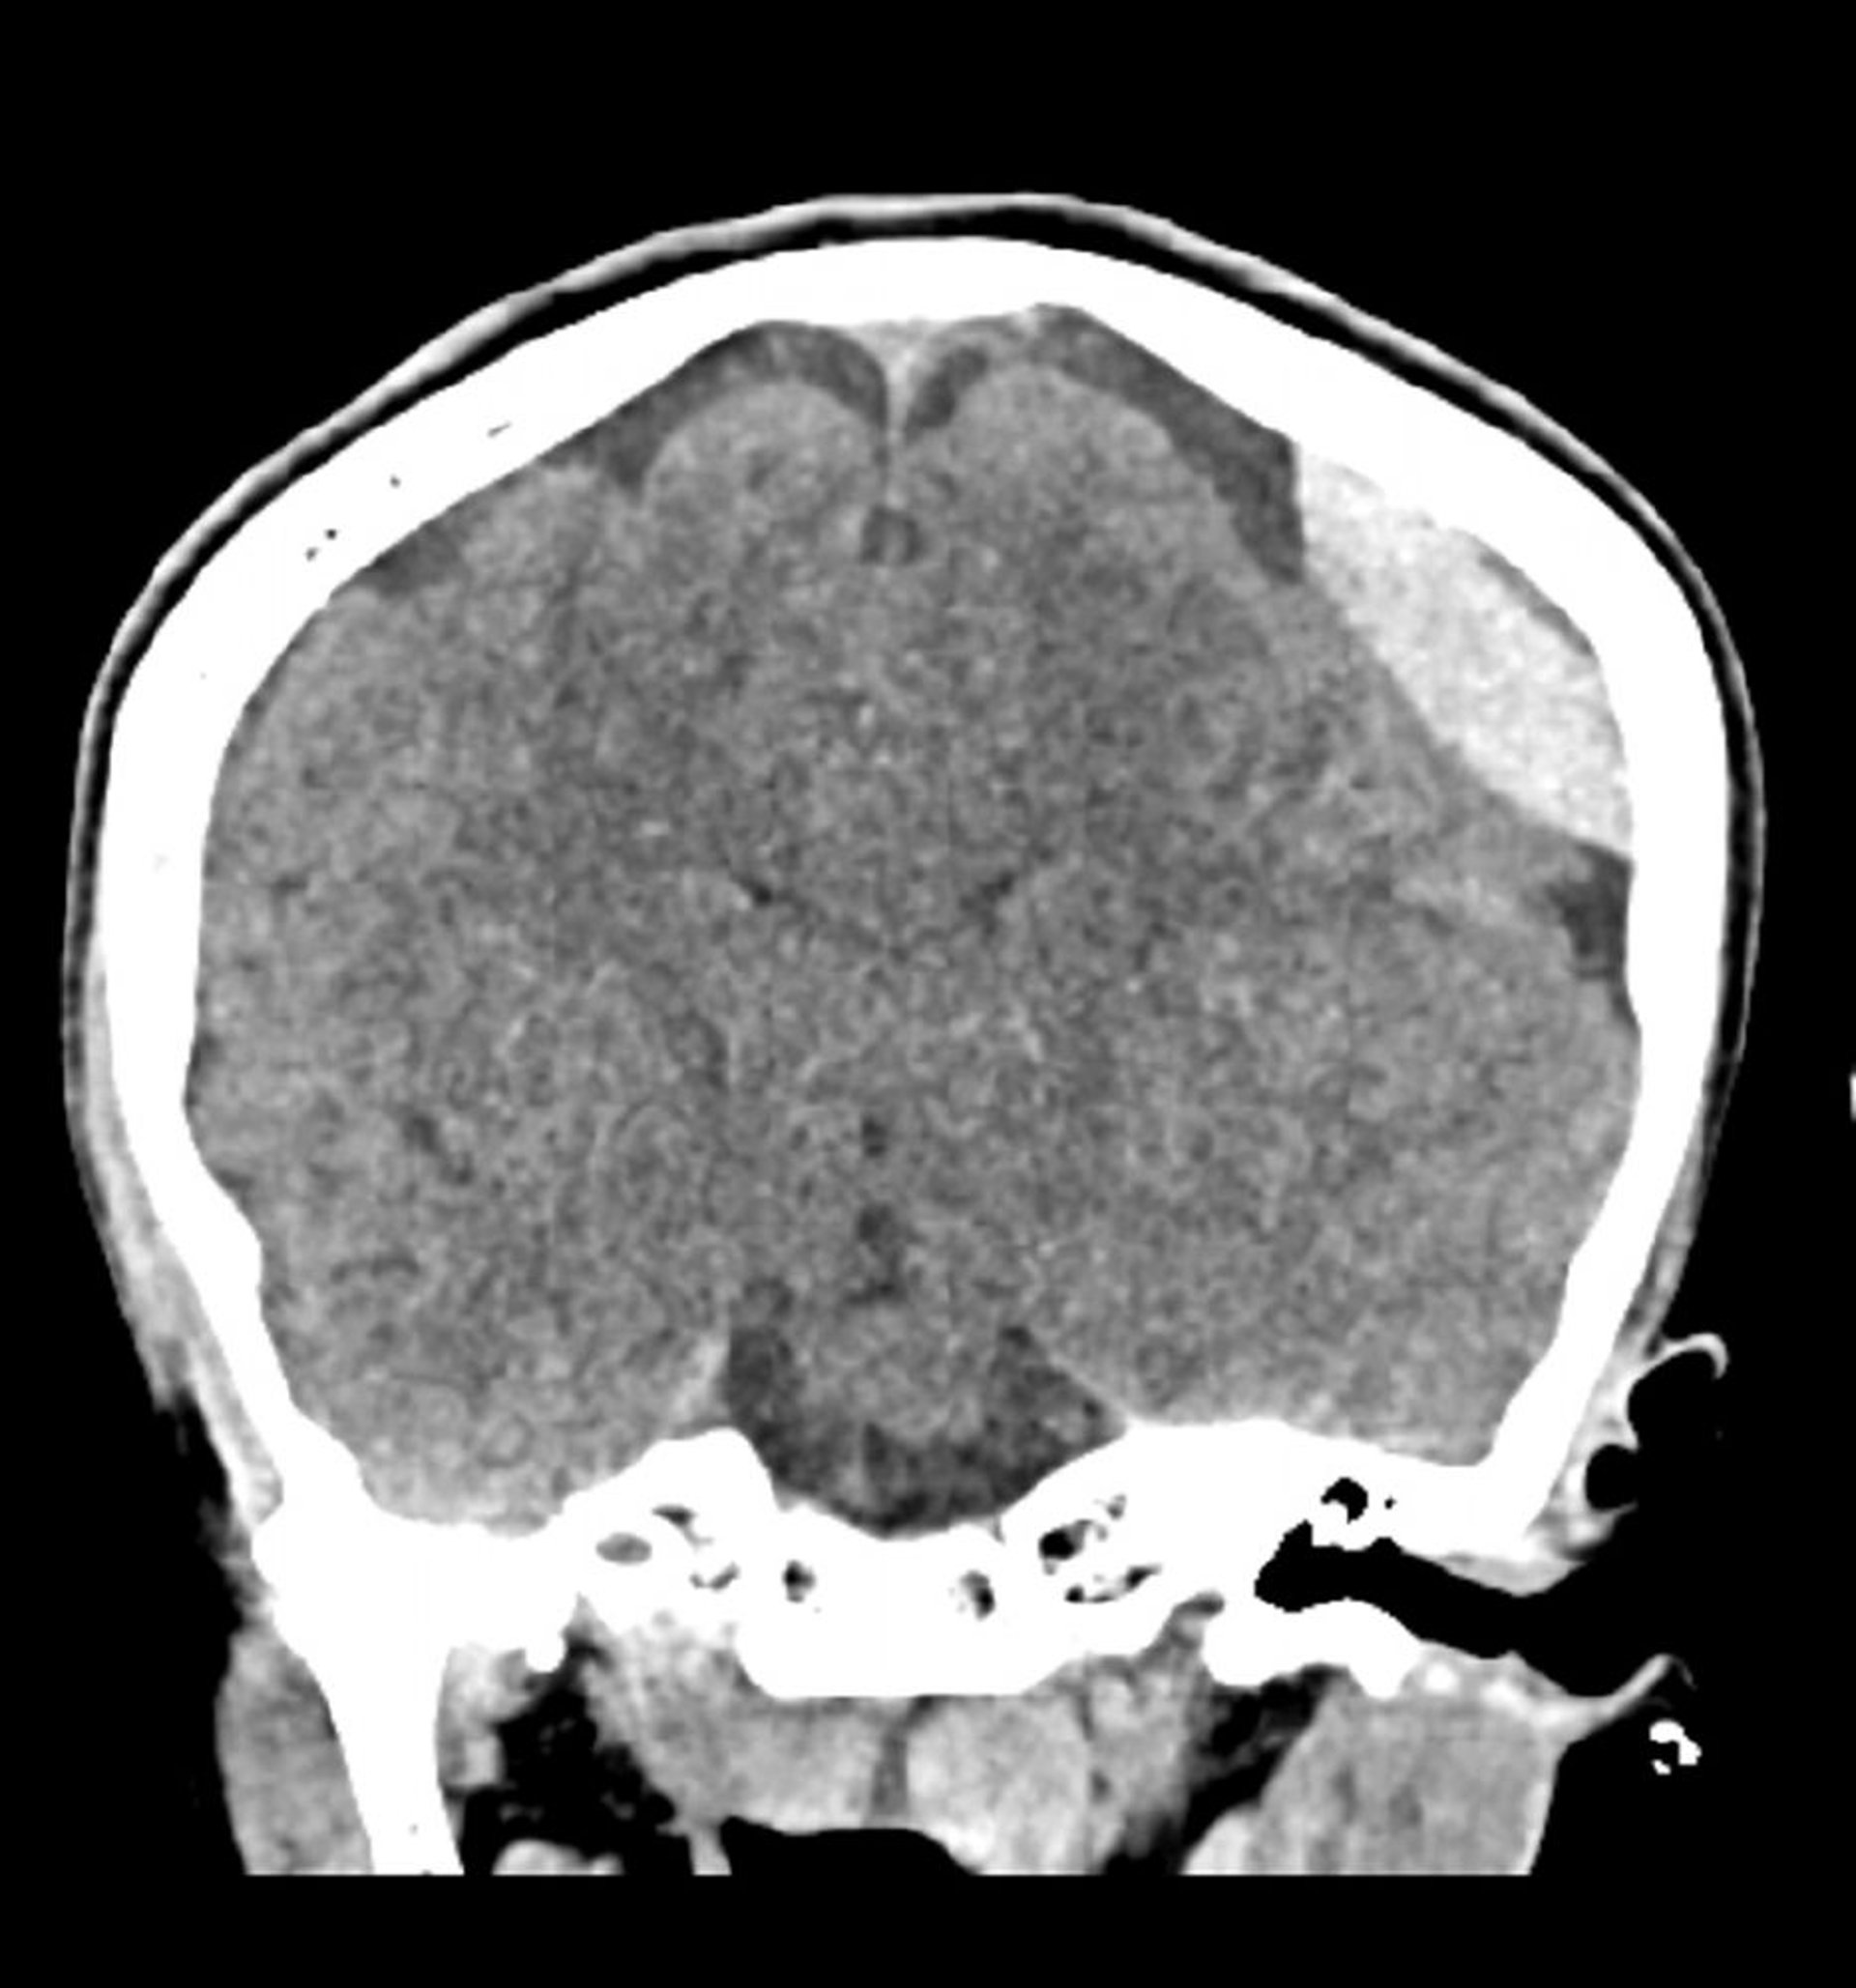

Epiduralblutung (Koronale CT)

Klassische linsenförmige (Linsen) -förmige Hyperdichte, die sich nicht über die Nahtlinien erstreckt.